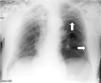

Varón de 71 años con criterios de EPOC grave (FEV1 38%), que ingresa en la UCI por insuficiencia respiratoria hipoxémica grave secundaria a infección respiratoria iniciándose antibioterapia empírica, tratamiento broncodilatador y ventilación mecánica invasiva. En la radiografía de tórax tras intubación (fig. 1) se objetiva imagen compatible con neumotórax izquierdo y se coloca tubo de tórax lateral sin fuga evidente, por lo que realizamos ecografía con signos de persistencia del neumotórax: líneas A, punto pulmonar (fig. 2) y ausencia de deslizamiento pleural. Ante la duda clínica se solicita TC torácica (fig. 3) en la que se identifica una imagen radiolucente redondeada de 10×8,5cm con pared fina sugestiva de ampolla anterior, sin línea clara de neumotórax. En pacientes con enfisema bulloso la ecografía pulmonar puede perder especificidad en el diagnóstico de neumotórax.